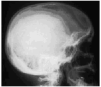

Se realizaron radiografías simples de las zonas que presentaban alteraciones cutáneas que permitieron descubrir un segundo fragmento metálico en la fosa antecubital y cuatro en la sien derecha (Fig. 3). En un segundo tiempo se extrajeron dichos fragmentos metálicos, que ya habían ocasionado una reacción fibroblástica y de células gigantes tipo cuerpo extraño en los tejidos adyacentes.

FIG. 3.--Radiografía simple de cráneo que muestra la presencia de cuatro objetos metálicos punzantes en sien derecha.